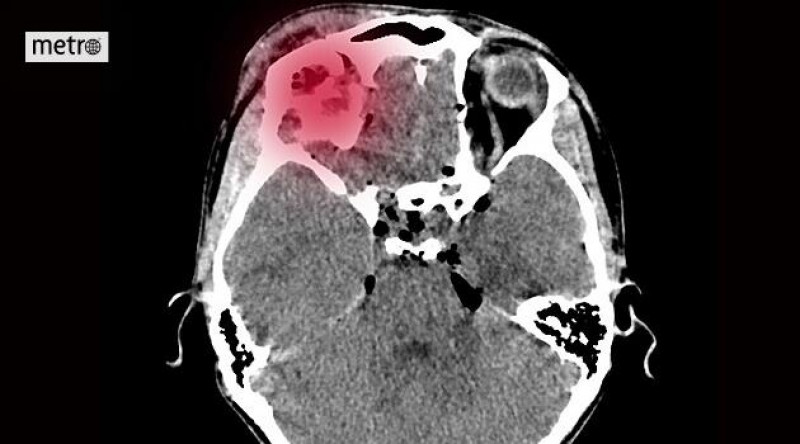

Nemocnice AGEL Ostrava-Vítkovice pořádá 13. května Den prevence cévní mozkové příhody, na kterém budou moci zájemci podstoupit bezplatná odborná vyšetření, jako měření krevního tlaku a ultrazvukové vyšetření přívodných mozkových tepen, aby zvýšili povědomí o příznacích mrtvice, která se netýká pouze seniorů a ročně má vážné důsledky včetně úmrtí tisíců lidí v ČR. #CévníMozkováPříhoda #Prevence #Zdraví

Mrtvice se netýká jen seniorů. Přijďte na Den prevence cévní mozkové příhody